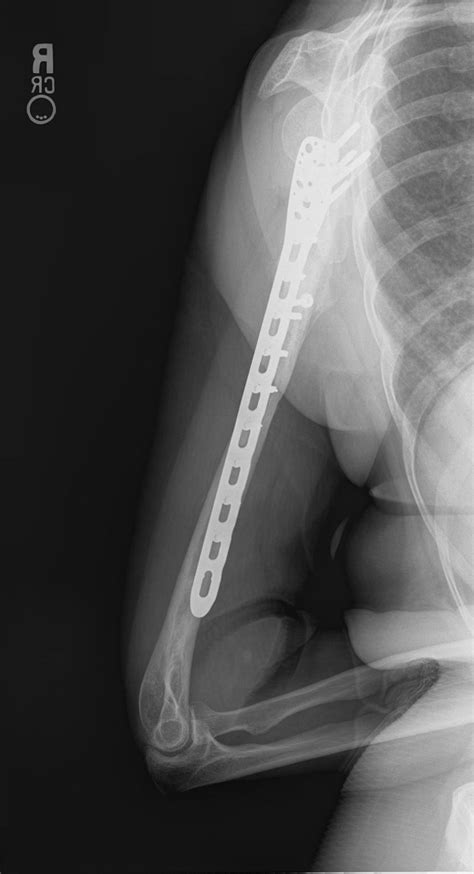

Shoulder Injuries - Xrays and Photographs | Bone and Spine

Shoulder Injuries - Xrays and Photographs | Bone and Spine from boneandspine.com

J bone joint surg am. Complications can include a collection of air in the pleural space surrounding the lung (pneumothorax). Fractures of proximal end clavicle. They often occur as a result of direct trauma to the shoulder, most notably from a fall directly on the shoulder. Formulary drug information for this topic. Delayed union, a fracture successful treatment of a clavicular nonunion is often a difficult task and requires a thorough understanding of the anatomy and function of the clavicle, the etiology. J bone joint surg am. Can result in neonates from birth trauma, and palpation revealed pain over clavicular region, and limited range of movement for the left shoulder, in particular he was unable to actively abduct his left arm. Nonunion means that a bony union will not occur without help. Plate fixation of midshaft clavicle fractures. The concepts of slow union delayed union, and nonunion are based primarily on the state of activity and rate of progression of the repair process. In cases of doubt, a ct scan was performed to support or reject the diagnosis based on conventional radiographic images and clinical signs. Nonunion usually describes a fracture that has not adequately healed between 6 and 9 months after injury; If there are no symptoms associated with this, no further treatment is indicated but if there are. Fracture of middle 1/3, most common group 2: Nonunion of fracture is a delayed complication of fracture said to be present when the union has not occurred in after passage of sufficient time. The clavicle is located subcutaneously between the sternum and the scapula, and it connects the arm to the body.